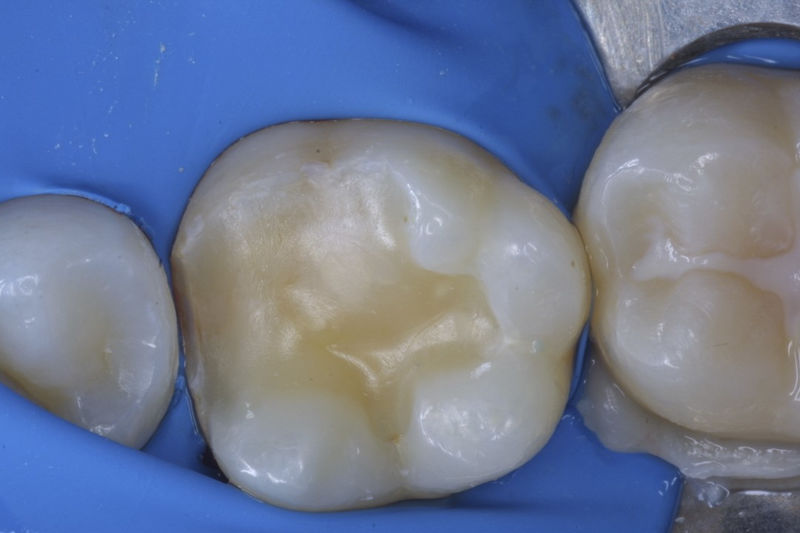

Restauraciones fabricadas en el laboratorio con materiales estéticos, los cuales cubren de manera parcial dientes posteriores. Se utilizan primariamente para restaurar dientes con caries, fracturas y/o defectos amplios. Para poder enviar el caso al laboratorio se toman impresiones utilizando materiales de impresión o técnicas modernas digitales.

Disciplina fundamental de la Odontología enfocada en el diagnóstico, prevención y tratamiento restaurador de las piezas dentales que han sufrido daños. Su objetivo principal es devolver al diente su equilibrio biológico, funcional y estético cuando su integridad ha sido alterada. Resinas directas, incrustaciones, coronas.